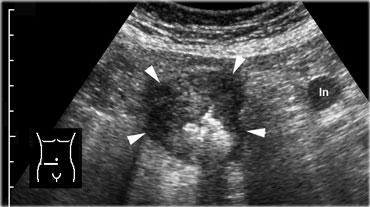

Ung thư manh tràng. Siêu âm cho thấy hình ảnh dày thành manh tràng không đối xứng, giảm âm, toàn chu vi (đầu mũi tên) kèm hẹp lòng ruột. Có một hạch bạch huyết to bệnh lý.

Bệnh nhân ung thư manh tràng có thể biểu hiện với các triệu chứng bụng cấp tính hoặc bán cấp theo nhiều hình thức khác nhau.

Khối u có thể gây tắc ruột non cấp tính, xâm lấn ruột thừa, vỡ thủng hoặc bản thân khối u có thể gây đau trực tiếp.

Đặc tính thường gặp là khối u có kích thước lớn và đại tràng phải nằm gần thành bụng, khiến ung thư manh tràng trong hầu hết các trường hợp khá dễ nhận thấy trên siêu âm.

Phần lớn biểu hiện dưới dạng dày thành manh tràng không đều, không đối xứng, giảm âm, đặc, tăng sinh mạch máu (Hình).

Có thể tìm thấy các hạch bạch huyết mạc treo to ở vùng lân cận, và trong hầu hết các trường hợp cũng có một ít tổ chức mỡ viêm xung quanh khối u.

Trong một số ít trường hợp, khối u thuộc thể xơ cứng (scirrhous), loại này khó phát hiện hơn.

Việc phát hiện di căn gan tất nhiên là bằng chứng mạnh mẽ ủng hộ chẩn đoán ác tính.